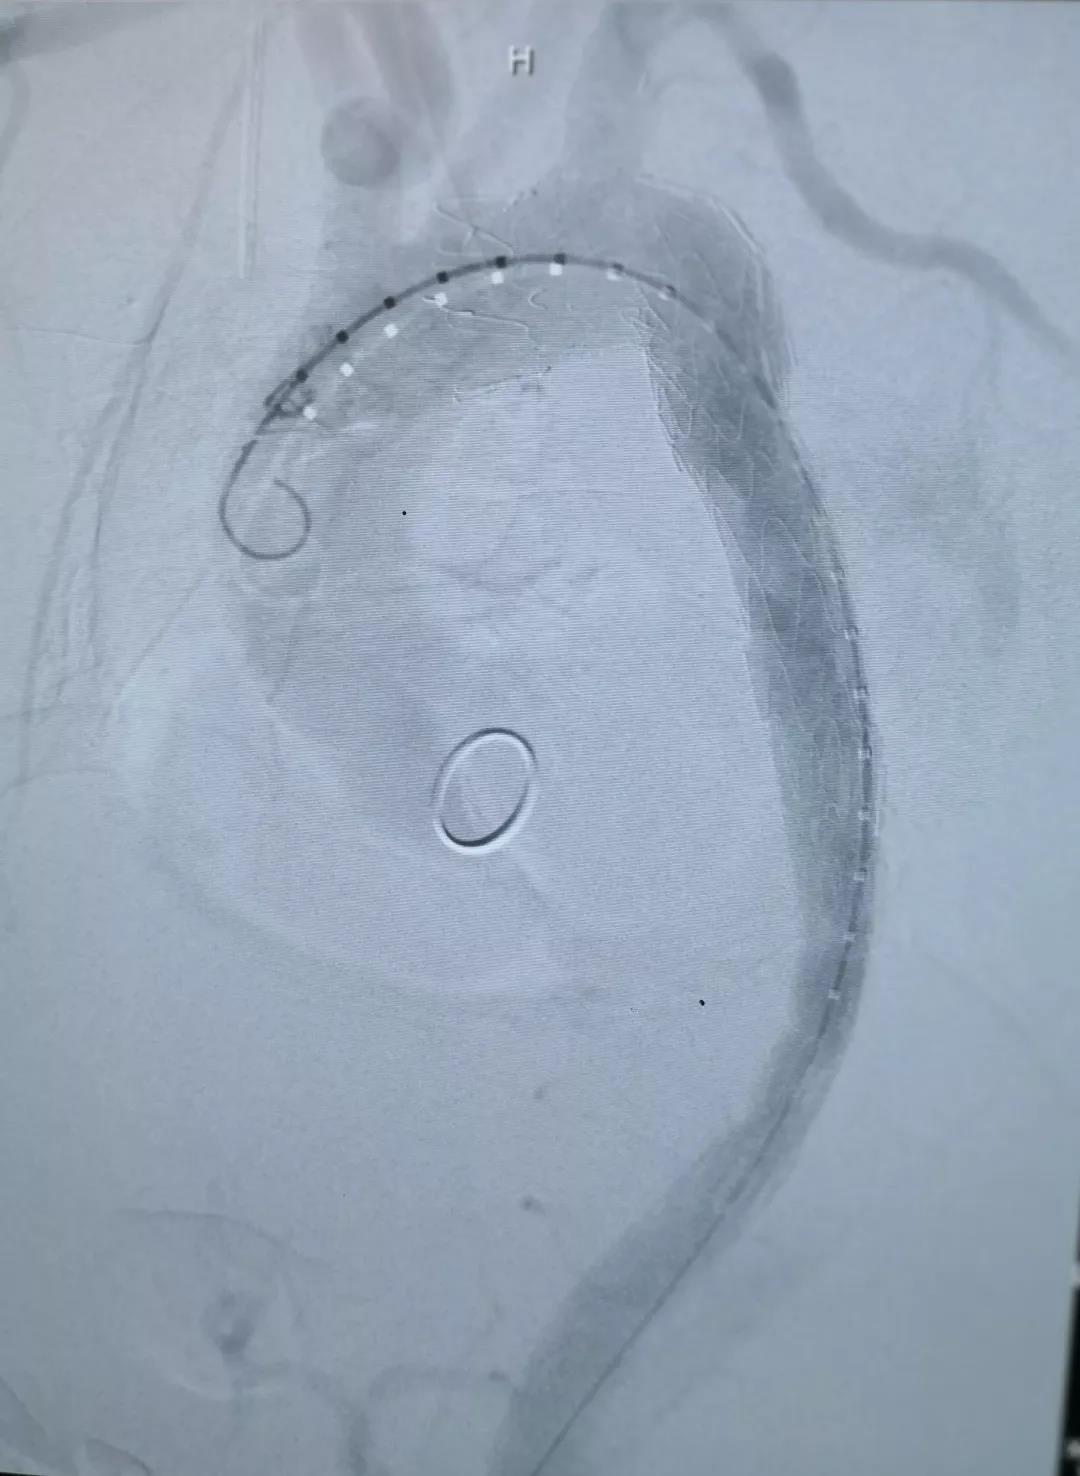

术中通过DSA造影显示:主动脉夹层破口位于左锁骨下动脉近端,真腔压闭。舒畅教授通过左锁骨下动脉预置Longuette™裙边支架,释放 Ankura™ Pro主动脉主体覆膜支架,封堵破口后通过裙边支架显影点准确定位,释放裙边支架,凭借着舒畅教授精湛的手术操作和器械的优异性能,手术过程非常顺利,胸主动脉支架释放良好,患者的主动脉夹层破口封闭良好,左锁骨下动脉释放的裙边支架血流通畅,没有内漏发生。由于患者远端真腔较小,为了保证远端的血流,植入了一个cuff支架,造影显示远端真腔打开良好。

(图:术后造影)